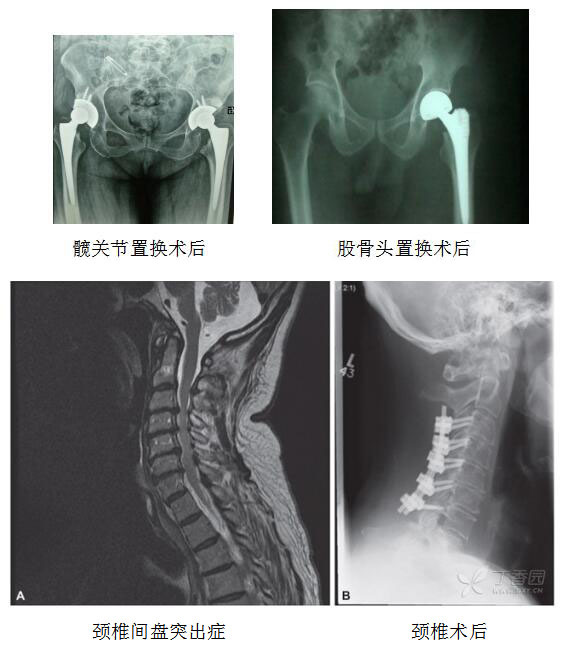

科室常规诊疗项目:开展四肢骨折、关节内骨折等创伤所致骨折手术:对颈椎间盘突出症、胸椎间盘突出症、腰椎间盘突出症采用全椎板、半椎板切除髓核摘除术,人工椎间盘置换术;对股骨头坏死、类风湿性关节炎、陈旧性股骨颈骨折并严重变形、塌陷和继发髋关节骨性关节炎、髋臼破坏中或有明显退变行人工髋关节置换,用带旋髂深血管骨瓣移植治疗股骨头早期坏死,微创小切口治疗股骨颈骨折、股骨干骨折、胫骨骨折等手术,肋骨骨折复位内固定术,神经、血管断裂吻合术,应用微创外固定技术治疗骨折、骨关节病及四肢畸形。解决了粉碎性骨折、骨关节病与四肢畸形的微创快速治疗难题,更适合膝踝畸形矫正及骨性关节炎的牵张治疗。开展微创外固定支架技术治疗骨不连、感染性骨折、骨缺损等;四肢骨与关节畸形;四肢挫灭伤保肢;应用中医正骨手法复位或微创小切口新型外固定支架固定治疗,不用二次手术取出内固定物,较传统手术治疗骨折愈合快、并发症少。

髋关节矫形器适应症:髋关节脱位术后;臀肌替代术后;髋关节置换术后